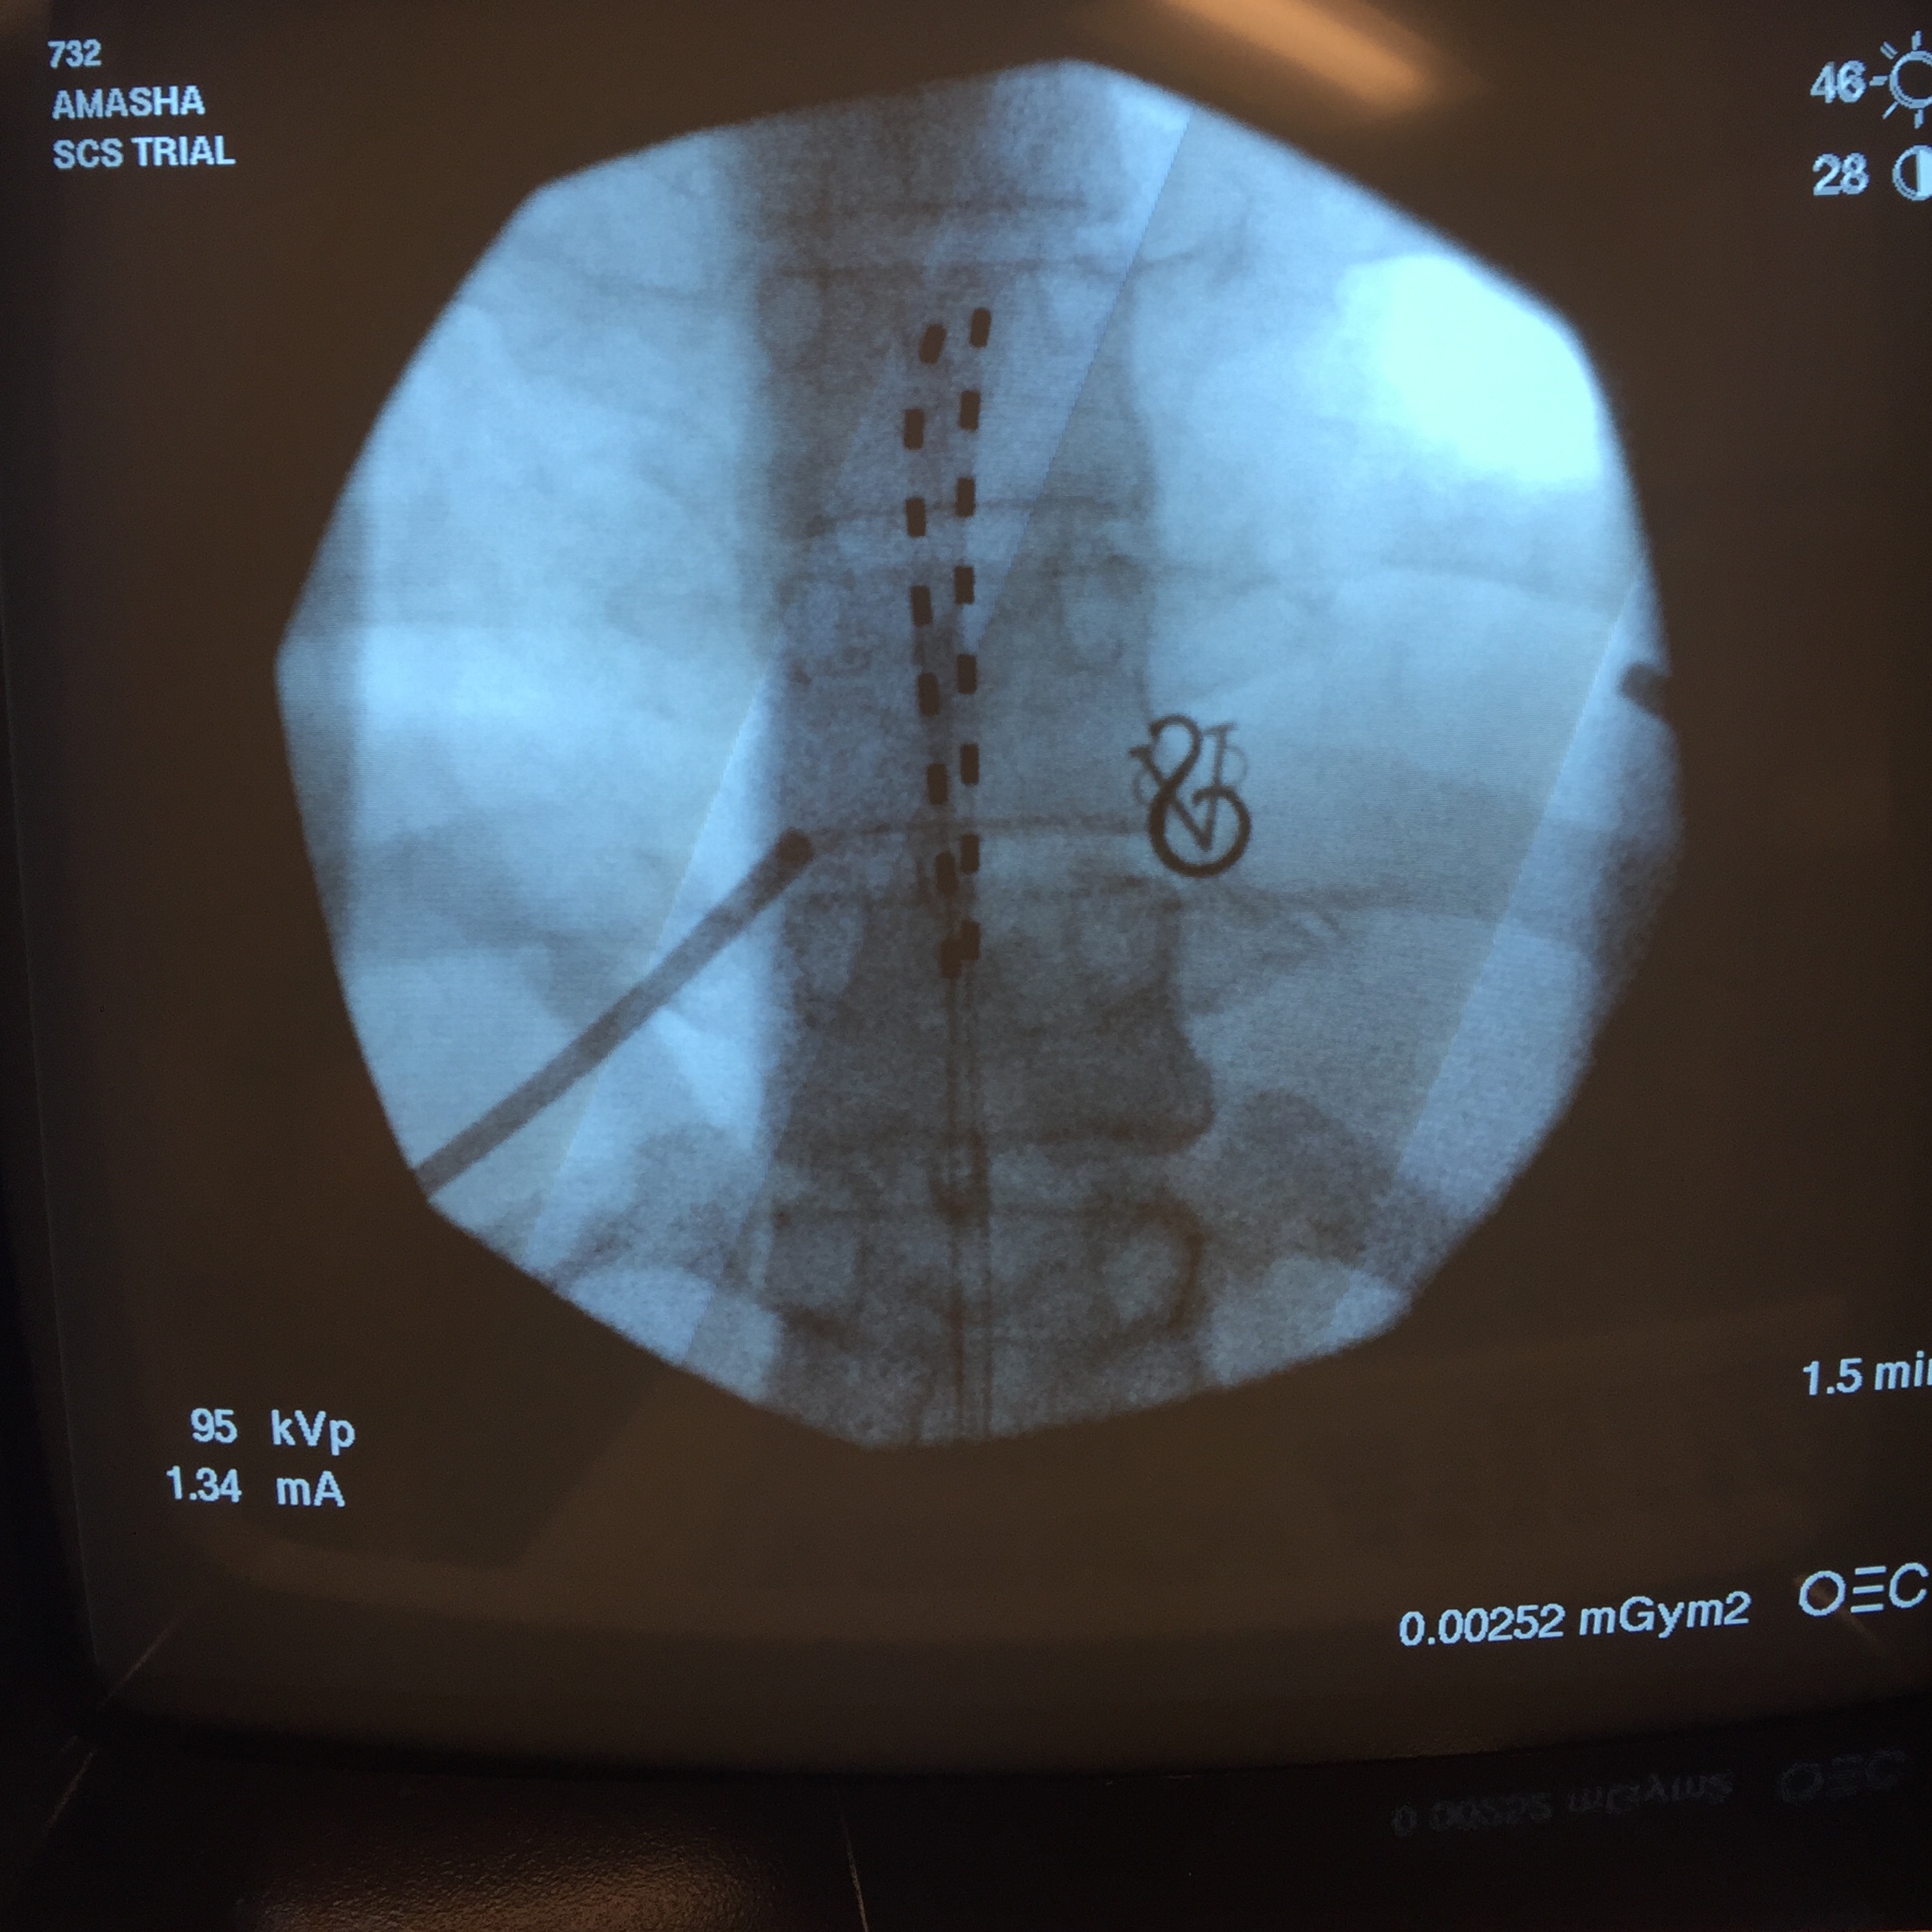

Before getting a long-term implant, we had to make sure it would work for me. First, I had to do three lumbar injections of steroids to make sure the stim would be placed in the right spot. Then I got to take a trial run with the stimulator technology.

This was a try-before-you-buy treatment. Using X-ray fluoroscopy to guide a hollow needle, they insert electrodes into the space between bone and spinal cord, positioning this trial lead over specific nerves they think are causing the pain. The wires exit the body and connect to an external battery.

test leads in spine

Janet Jay

Doctors tape everything down very well, caution you not to shower (apologies to my husband), and give you a controller and a weird corset-like brace to hold everything in place. Then they send you home to see if it helps. I asked Timothy Deer, president and chief executive officer of The Center for Pain Relief in Charleston, West Virginia, about my chances. In his experience, someone with my diagnosis has about a 70 percent chance of the trial alleviating pain; however, he said if it did help, the odds are more like 90 percent that the actual surgery will work.